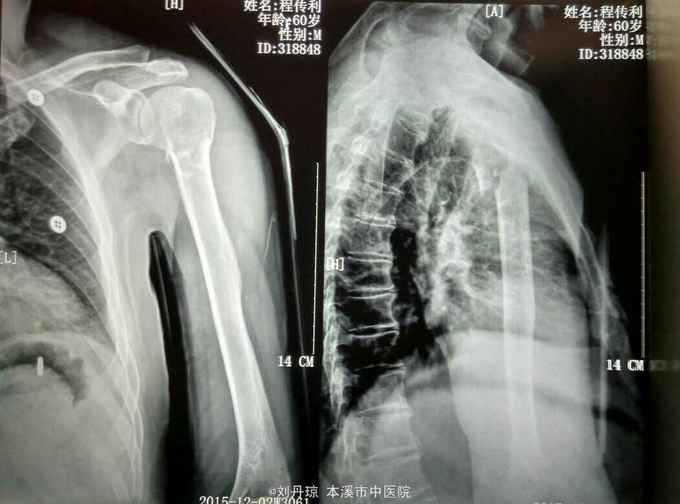

诊断:左肱骨近端粉碎骨折 治疗:手法整复,夹板固定。接骨丹口服。

随访1年。此四部分骨折,肱骨近端四个解剖部分完全分离,肱骨头移向后方,肱骨头血运破坏严重,容易发生缺血坏死。